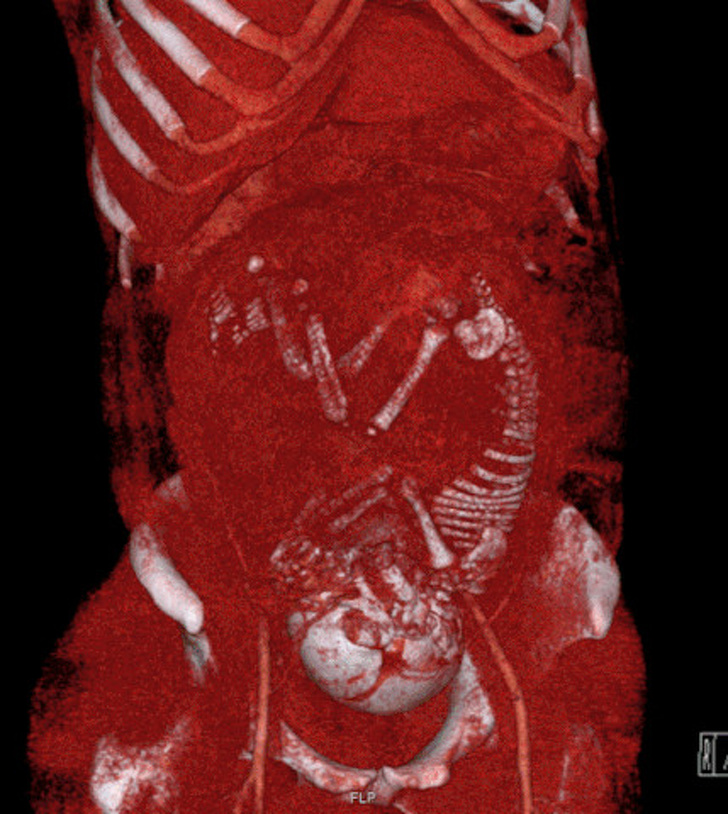

1. Комп'ютерна томографія жінки на 37-му тижні вагітності